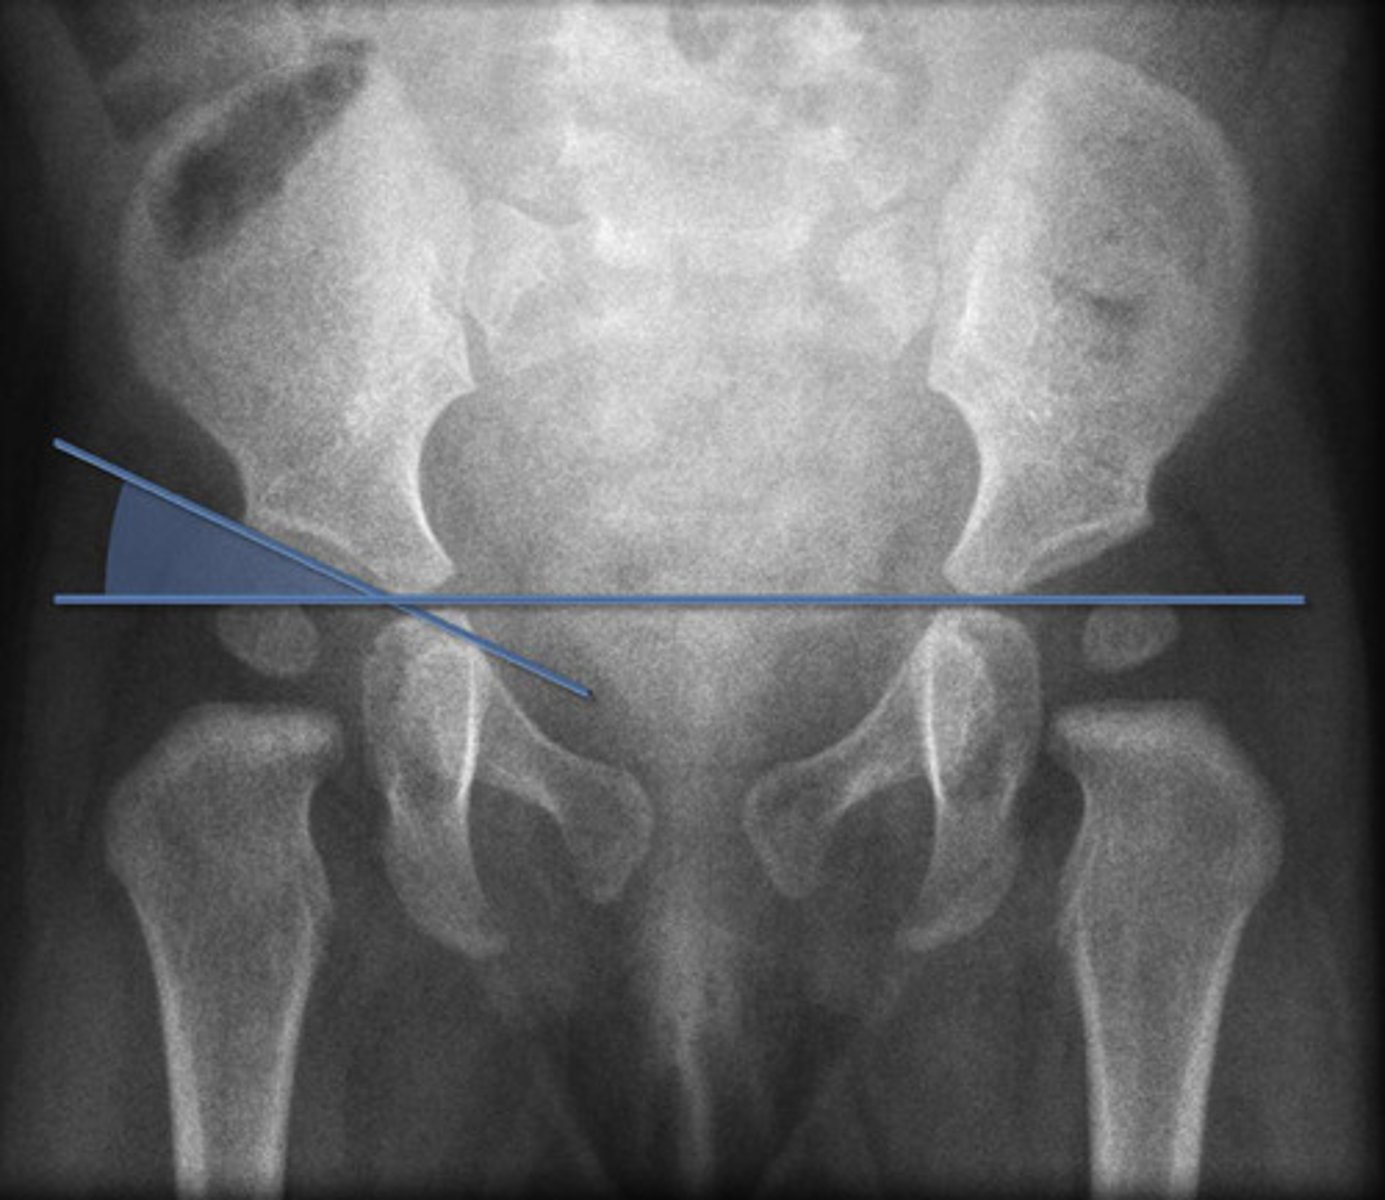

Hilgenreiner's Line

Used for assessment of DDH

Line drawn horizontally, connecting the inferior aspect of the tri-radiate cartilages bilaterally >> femoral head should be below this line

Perkin's Line

Line drawn vertically through the lateral most aspect of the acetabular roof perpendicular to Hilgenreiner's line

The ossified femoral head should be located in the inferomedial quadrant created

Acetabular Angle

Angle measured between Hilgenreiner's line and a line parallel to the acetabular roof